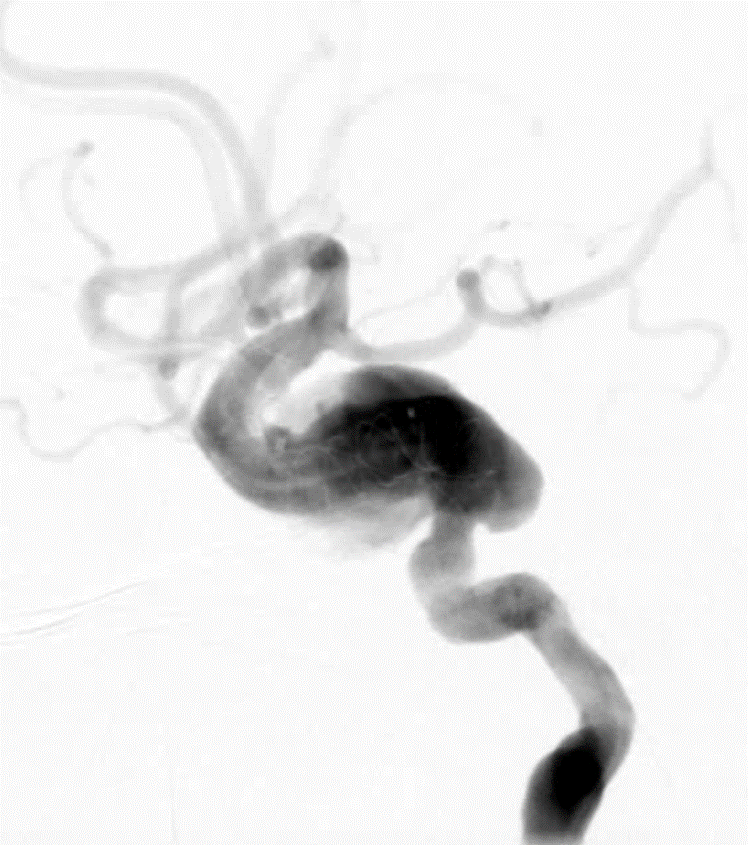

- 新路图下,沿微导管依次填入数枚弹簧圈,将动脉瘤填塞。复查造影证实动脉瘤达完全栓塞,载瘤动脉通畅。

动脉长鞘怎么置入深谋远路 | 千人皆翘首,万唤今始来——国内首款7F长鞘在血流导向密网支架联合弹簧圈栓塞治疗动脉瘤的首次应用_https://www.jmylbn.com_新闻资讯_第27张术后正位造影

动脉长鞘怎么置入深谋远路 | 千人皆翘首,万唤今始来——国内首款7F长鞘在血流导向密网支架联合弹簧圈栓塞治疗动脉瘤的首次应用_https://www.jmylbn.com_新闻资讯_第28张

术后侧位造影